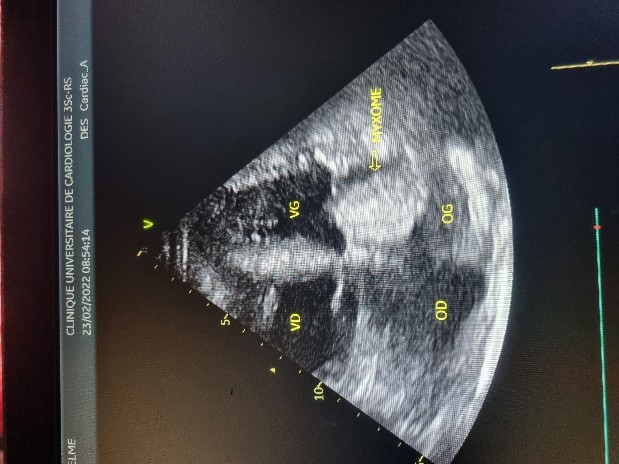

L’électrocardiogramme notait un rythme sinusal régulier avec une fréquence cardiaque à 83 bpm, des anomalies de la repolarisation en antéro septal à type d’ondes T biphasiques et en inférieur à type d’ondes T négatives asymétriques. La biologie était normale. L’échocardiographie (transthoracique et transœsophagienne) retrouvait les mêmes caractéristiques avec une masse appendue à la face atriale de la grande valve mitrale, obstruant partiellement l’orifice mitral et mesurant 49mm ×27 mm. Elle faisait protrusion dans le ventricule gauche en diastole (Figures 5 et 6). Cette masse était évocatrice d’un myxome de l’oreillette gauche. Le ventricule gauche n’était pas dilaté (DTDVG= 46mm), avec une fraction d’éjection systolique à 74% au Simpson biplan. Les pressions de remplissage du ventricule gauche étaient élevées. L’oreillette gauche était dilatée (VOG= 43mL/m²). Les cavités droites n’étaient pas dilatées. La fonction ventriculaire droite était normale (TAPSE= 24mm). On notait une hypertension pulmonaire avec PAPS =75mmHg, VmaxIT= 4,18 m/s. La veine cave inférieure était fine et compliante.

Figure 5 (a, b et c): Echocardiographie transthoracique en mode bi dimensionnel montrant un large myxome de l’oreillette gauche appendu à la face atriale de la grande valve mitrale faisant protrusion dans le ventricule gauche en diastole vu en incidence apicale 4 cavités (a et b) et 2 cavités avec doppler couleur notifiant une insuffisance mitrale (c) chez un patient de 57 ans. (Cas clinique n° 3). VG= ventricule gauche ; OG= oreillette gauche ; OD= oreillette droite ; VD= ventricule droit

Figure 6: Echocardiographie transoesophagienne en bi dimensionnelle, incidence 4 cavités vue bi-commissurale montrant un myxome appendu à la face atriale de la grande valve mitrale et faisant protrusion dans le ventricule gauche en diastole (Cas clinique n°3). VG= ventricule gauche ; OG= oreillette gauche.